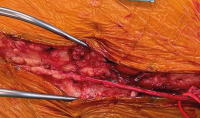

Die koronare Bypassoperation – Indikationen, Risikoabwägung, neue Techniken und Nachsorge // Coronary bypass surgery – Indications, risks, new techniques and postoperative care

Journal für Kardiologie - Austrian Journal of Cardiology 2022; 29 (9-10): 254-256 Volltext (PDF) Summary Abbildungen